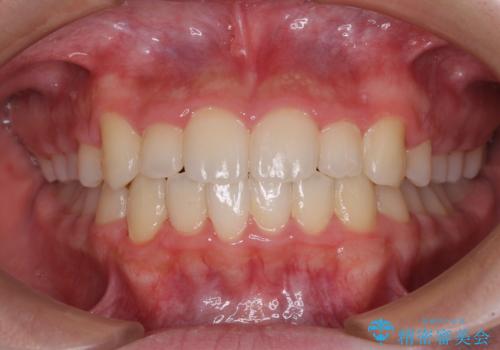

中学生のワイヤー矯正 クロスバイトを短期間で改善

- 前歯のクロスバイトを気にして来院された患者様です。

中学生であることから、治療期間を短縮できると判断し、ワイヤー矯正にて短期間で治療を行うこととしました。

叢生のため磨き残しの多い歯列でしたが、1年弱で治療を終了でき、磨き残しや歯肉の腫れが著しく改善されました。